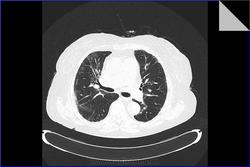

Идиопатический фиброзирующий альвеолит. Пациентке 79 лет. Диагноз поставлен 3 года назад. Лечится гормонами. Клинически за 3 года наросла одышка. Данные прошлых исследований не предоставлены. Заинтересовали размеры легочной артерии. Основной ствол - 37 мм (N=29 мм), правая ветвь 33 мм (N=24 мм), левая ветвь 28 мм (N=28 мм). Интересно, почему степень расширения левой легочной артерии отстает от правой и основного ствола. Обусловлено ли это разными углами отхождения ветвей или может косвенно характеризовать степень вовлеченности легочной ткани каждого легкого в фиброзирующий процесс?

Идиопатический фиброзирующий альвеолит. Пациентке 79 лет. Диагноз поставлен 3 года назад. Лечится гормонами. Клинически за 3 года наросла одышка. Данные прошлых исследований не предоставлены. Заинтересовали размеры легочной артерии. Основной ствол - 37 мм (N=29 мм), правая ветвь 33 мм (N=24 мм), левая ветвь 28 мм (N=28 мм). Интересно, почему степень расширения левой легочной артерии отстает от правой и основного ствола. Обусловлено ли это разными углами отхождения ветвей или может косвенно характеризовать степень вовлеченности легочной ткани каждого легкого в фиброзирующий процесс?

////Интересно, почему степень расширения левой легочной артерии отстает от правой и основного ствола./// - Это не имеет значения. Главное , что легочный ствол больше 29мм. Если найдете обратное, поделитесь, пожалуйста.

Правая ветвь - измерение по крайним точкам, ЛА и левая ветвь - линейка заходит на пределы сосуда). Не думаю, что тут разница в 5 мм... скорее 2-3, что вполне допустимо.

Некоторые исследователи считают, что верхняя граница нормы ствола ЛА составляет 32,6 мм... "the CT-determined mean pulmonary artery diameter was 26.6 ± 2.9 mm. The mean MPAD in males was 27 ± 2.8 mm, and 25.9 ± 3.0 mm in females ... The present study demonstrated that in individuals with normal pulmonary artery pressure, the upper limit of the MPAD is 32.6 mm and that MPAD is wellcorrelated with BSA. ." http://www.dirjournal.org/pdf/pdf_DIR_164.pdf

Другие - что 33 мм: http://translate.googleusercontent.com/translate_c?hl=ru&langpair=en%7Cru&rurl=translate.google.ru&twu=1&u=http://bjr.birjournals.org/content/76/901/79.1.full&usg=ALkJrhg_BCJlhUs34PaftNIJega6IUPlsQ

Для легочного идиопатического фиброза = криптогенного фиброзирующего альвеолита изменения не выражены - может, адекватная терапия. Либо одышка и ДН по другой причине. Если брали биопсию - вопросов нет, а если нет, то есть)))